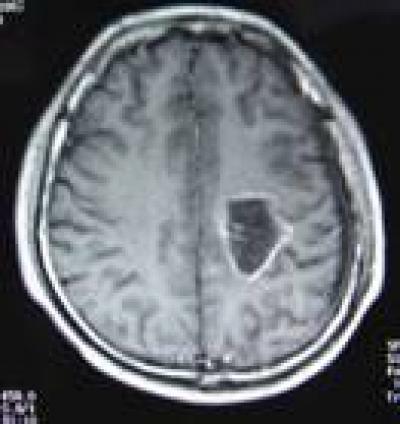

Malignant glioma is very sensitive to heat. Prof. Yunlong Ge and team from the Second Affiliated Hospital of Harbin Medical University, China used a brain tumor hyperthermia apparatus to treat malignant glioma patients, and achieved good therapeutic efficacy. The researchers found that the blood-brain barrier within and surrounding the tumor was completely destroyed after hyperthermia treatment, and chemotherapy drugs could then reach and target the tumor. Meanwhile, hyperthermia and radiotherapy could contribute synergistically to the treatment of brain glioma. These findings were published in the Neural Regeneration Research (Vol. 8, No. 29, 2013).